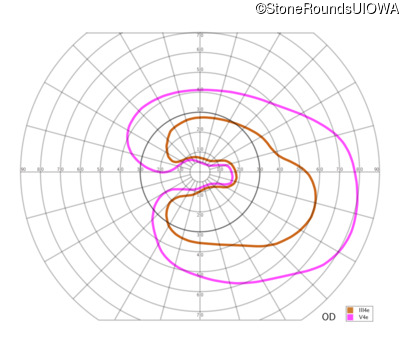

This 81 year old man began using a flashlight to read menus in his 40's. At age 75 his ophthalmologist noticed abnormal fundus findings and referred him to a retina specialist.

| Age at visit: 81 years |

| Age at visit: 82 years |

| Age at visit: 83 years |

| Age at visit: 84 years |

| Age at visit: 85+ (Visit 1) |

| Age at visit: 85+ (Visit 2) |